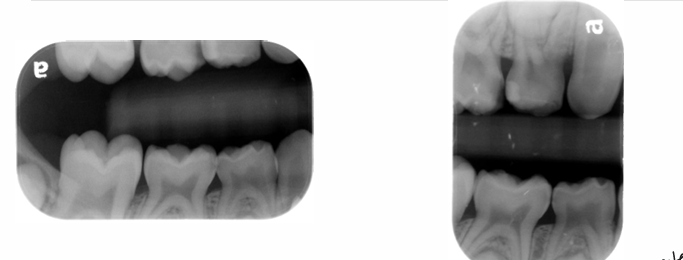

bite wing radiograph

-mesial surface of canine to distal surface of 1st permanent molar

-distal contact of canine to mesial contact of last tooth in arch

horizontal v. vertical bitewing

-vertical easier to tolerate for pts who gag